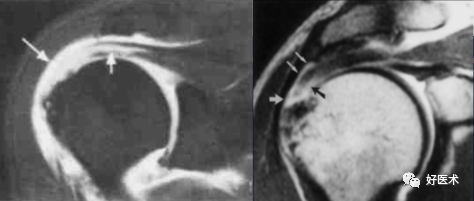

2)部分撕裂

-

肌腱增厚、变薄、不规则;

肌腱的关节面或滑膜面撕裂,或肌腱内分离缺损,肌腱连续性存在;

斜冠面T1WI 上呈低至中等信号强度,PDWI呈中等到高信号,T2WI +FS上呈高信号强度;

T2WI+FS,肩峰下滑囊和三角肌下滑囊不应出现高信号(积液)。

冈上肌腱不完全撕裂

冈上肌腱不完全撕裂伴肩峰下囊积液

冈上肌肌腱损伤(撞击),肩胛下滑囊积液(肩胛下肌腱损伤?)

冈上、下肌腱撕裂、肩胛下囊积液